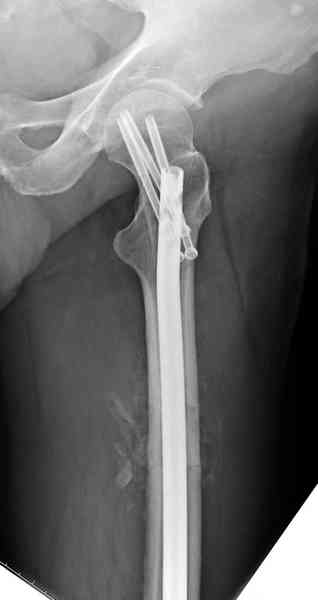

Здесь представлены снимки больного 65 лет, поступившего с диагнозом перелом

бедра после автоаварии.

В первый же день произведено антеградное штифтованием DePuy Trochanteric Nail.

На второй день (7) обнаружен пропущенный перелом,

и проведены шурурпы через и спереди штифта без удаления.

Послеоперационные снимки